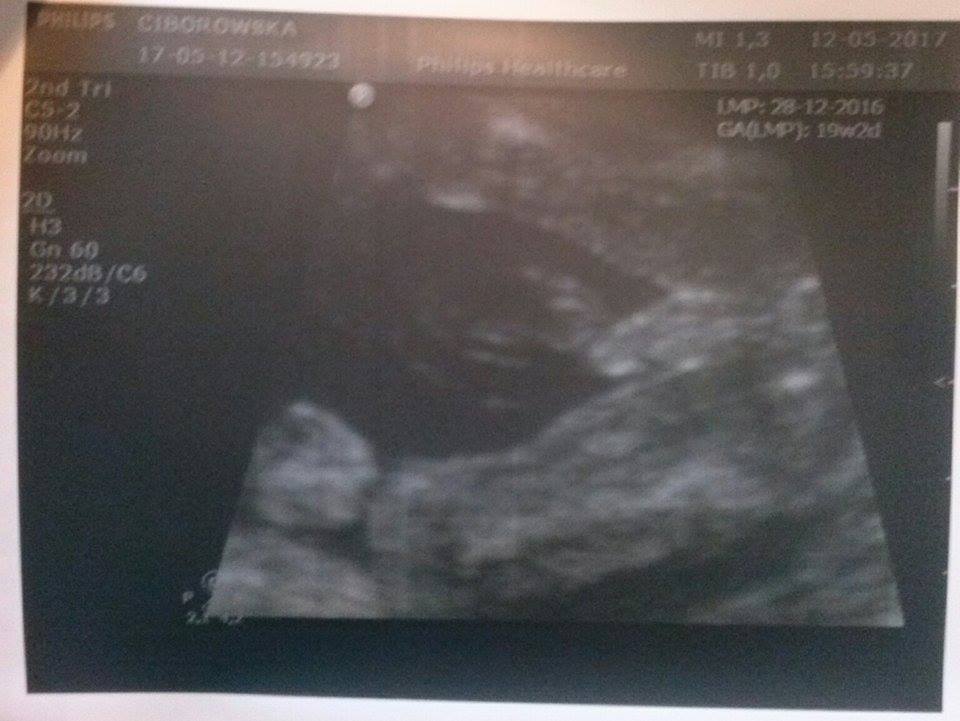

A to jego skarby między nogami... No i tu jest zamieszanie. Lekarka zdecydowanym głosem oświadczyła: "Dziewczynka". Jak jej powiedziałam, że poprzedni lekarz twierdził, że chłopiec, to się zaczęła długo przyglądać, pod różnym kątem i w końcu powiedziała: "Noo... może i chłopiec?"

Na koniec dodała: "Tak, to może być chłopiec".

Więc ja już nie wiem :0 A Wy jak myślicie? Są tu takie specjalistki od analizy zdjęć